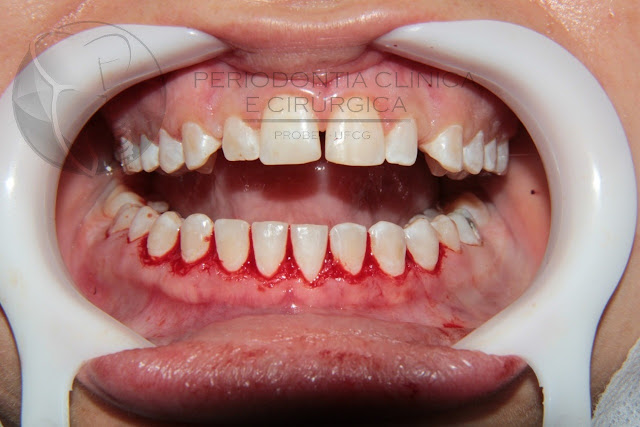

M.N.M, paciente do gênero feminino, sem alterações sistêmicas, 23 anos, sem ocorrência de inflamação gengival, detectado por meio de sondagem periodontal, compareceu ao Projeto de Extensão em Periodontia Clinica e Cirúrgica da UFCG. Ao exame clínico, constatou-se hiperplasia gengival superior e inferior (Figura 01) e histórico de tratamento ortodôntico. Após exames periodontais de rotina, constatou-se profundidade de sondagem e mucosa ceratinizada adequados para a indicação da técnica da gengivectomia e gengivoplastia. Este caso relata a cirurgia na região inferior. Paciente relatou ter removido o aparelho pouco tempo antes da cirurgia.

Figura 01– Aspecto clínico inicial. OBS.: Essa área vermelha na região do elemento 31 não é inflamação gengival. A foto foi tirada no momento em que já havia sido feita a sondagem periodontal do referido elemento.